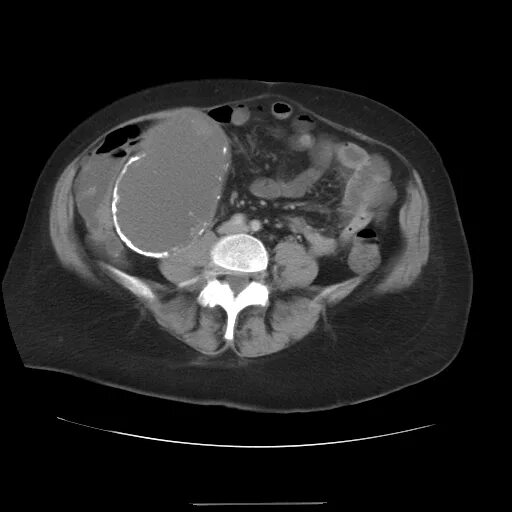

Солидные образования малый таз